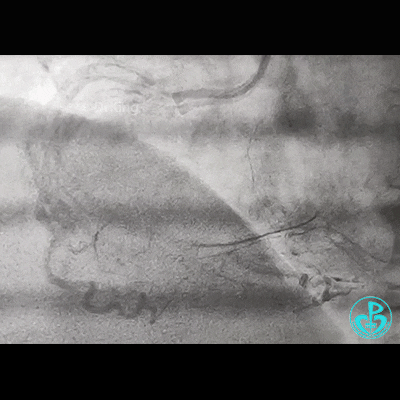

开始后扩,3.5×15mm后扩球囊不能进入近端支架口,GC系统飞出!故事开始。

重进导丝,比较顺利!3.5×15mm球囊仍不能通过支架近段!再进一根导丝,还不行!

导丝怎么扩右冠近段弥漫性病变中远段闭塞顺利开通并植入支架,哪知道故事才刚刚开始!!!_https://www.jmylbn.com_新闻资讯_第11张

考虑导丝可能从支架钢梁外进入,故调整GC,把两根导丝均Knuckle进入,再进球囊!不行!

导丝怎么扩右冠近段弥漫性病变中远段闭塞顺利开通并植入支架,哪知道故事才刚刚开始!!!_https://www.jmylbn.com_新闻资讯_第12张

导丝怎么扩右冠近段弥漫性病变中远段闭塞顺利开通并植入支架,哪知道故事才刚刚开始!!!_https://www.jmylbn.com_新闻资讯_第13张

因右锁骨下动脉迂曲打弯,GC张力过高,尝试GC深插,有阻力,不敢粗暴,稍微提出到开口,则立即飞出!

如此,反反复复,重进导丝,急切不能得手。